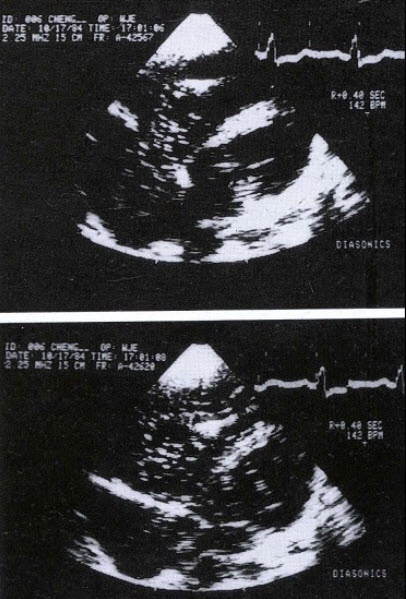

11、单项选择题

用于左心声学造影的造影剂有()

A.生理盐水

B.葡萄糖溶液

C.双氧水

D.声振微气泡造影剂

E.一氧化碳气体